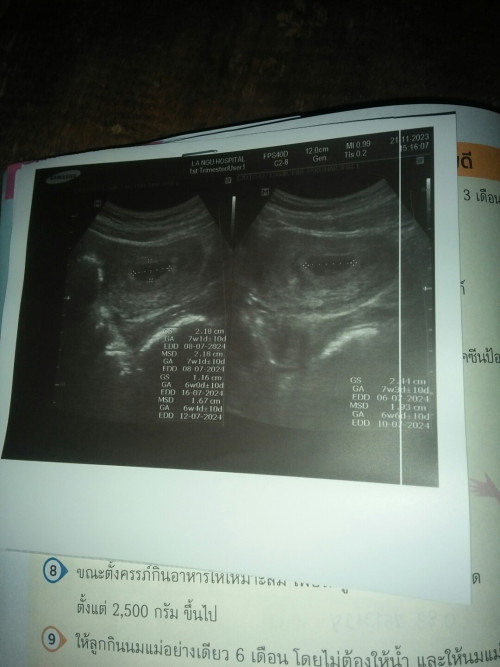

เมื่อวานไปหาหมอมา ไปฝากครรภ์คค่ะท้องแรก คุณหมอบอกว่า6สัปดาห์แล้ว แต่ซาวหน้าท้องยังไม่เจอตัวอ่อน ซาวทางช่องคลอดก็ยังไม่เห็น มีโอกาสเป็นท้องลมมั้ยค่ะ กังวลมากเลยค่ะ แต่ส่วนตัวไม่มีอาการเลือดออกใดๆ🥹#ท้องแรกคะ

เราไปซาวเมื่อวานนี่คะ 6สัปดาห์ เป็นตัวเล็กแล้วค่ะ มีหัวใจเต้นตุ๊บๆด้วย เราก็กลัวเหมือนกันค่ะกลัวเป็นท้องลม ขอให้คุณแม่เจอตัวเล็กนะคะ

ของเราก็เป็นค่ะ ไปตอน5w ยังไม่เจอตัวอ่อน เจอแต่ถุงตั้งครรภ์ คุณหมอนัดดูใหม่อีก2 อาทิตย์กังวลเช่นกันค่ะ

5wซาวทางช่องคลอดเจอเเค่ถุงค่ะเเม่ หมอเลยนัดมาเจอตอน7wหัวใจเต้นเเล้วค่ะ